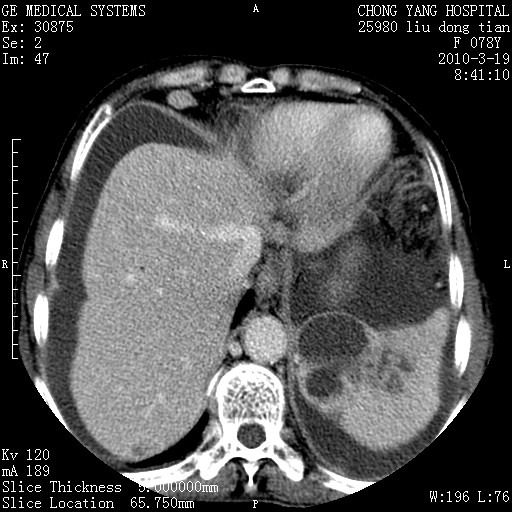

标题: CT25199:F 78Y 腹胀半年 消瘦乏力 [打印本页]

胆囊壁增厚并明显强化,胆囊癌伴多发转移瘤可能性大,淋巴瘤不除外,右肾囊肿,胸腹水.

考虑nhl,肝、脾、腹膜腔及腹膜后多发淋巴结受侵,腹水,右肾囊肿,慢性胆囊炎,右侧少量胸腔积液。

胆囊有软组织影有强化,支持胆囊癌,肝脾、腹膜后淋巴结转移。

nhl的淋巴结多围绕主动脉,而且主动脉会移位,所以不考虑nhl。

分开来讲:肝左叶、尾叶病灶有不均强化像肝癌;

脾脏病灶无强化,像多发囊肿或淋巴管瘤,不除外淋巴瘤(低强化);

胆囊增生性病变:胆囊癌,腺肌增生症,慢性胆囊炎;

肝门、胰腺头、腹膜后多个团块: 淋巴瘤,转移;

腔静脉肝内段细小有无布加可能?

一元论最好了 淋巴瘤所致改变; 胆囊癌转移不像,胆囊周围肝组织清晰,肝癌淋巴结转移?三元论都不止。

最后报的胰头癌多发转移,脾脏单独考虑囊肿或淋巴管瘤。